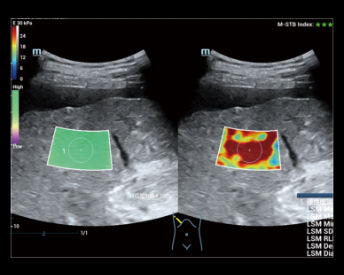

Premium Ultrasound System for Radiology

Resona R9

Powered by the revolutionary ZONE Sonography Technology, Resona R9 elevates clinical intelligence to a higher level with a complete solution. If precision diagnostic and interventional ultrasound is all you need, Resona R9 is your key to take a new leap.